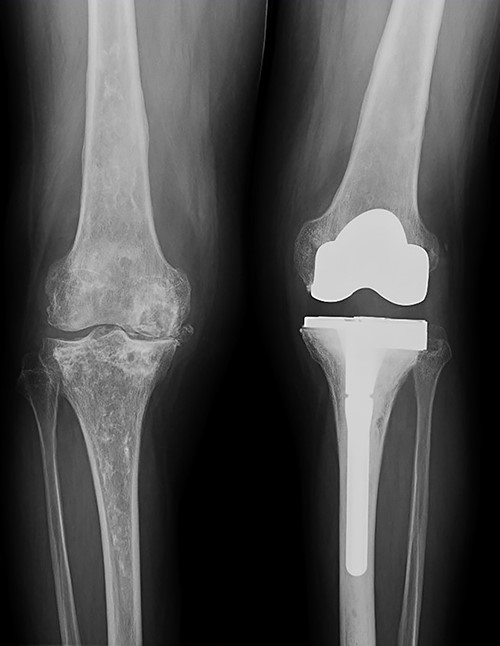

In the early postoperative period, no complications were detected, with pain decrease. After 4 years, the patient’s active ROM was 0–110° bilaterally, with no signs of radiological loosening (Fig. 9) and no pain, leading an unrestricted walking daily life without aids.

Both knees standing radiographs at 4-year follow-up with no signs of radiological loosening.